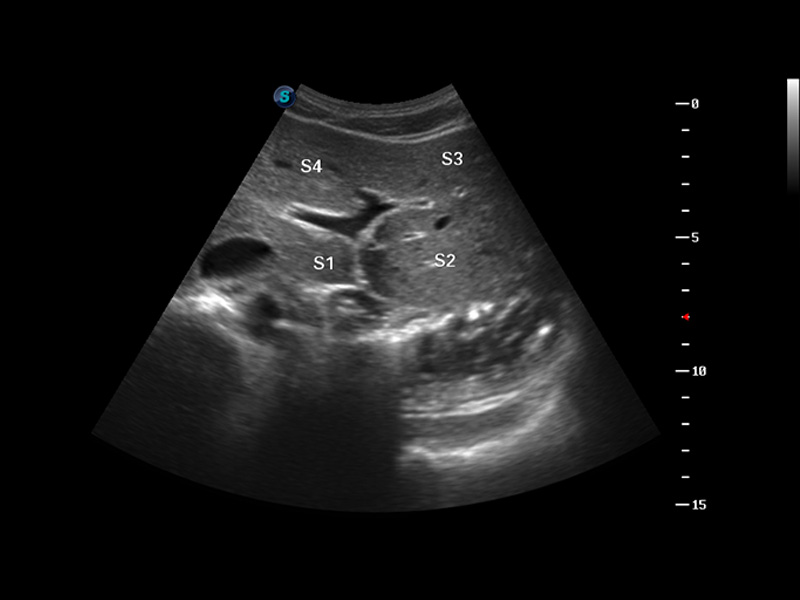

S8 EXP便携式彩色多普勒超声诊断仪是球速体育入口研发的高端全身应用型便携彩超。高通道的VIS平台融合可视化(Visual)、智能化(Intelligent)和人性化(Smart)的特点,配以球速体育入口自主研发生产的探头大家族,使您能够快速、准确的获得病人信息,提高工作效率的同时减轻疲劳。

成像技术

3D/4D成像